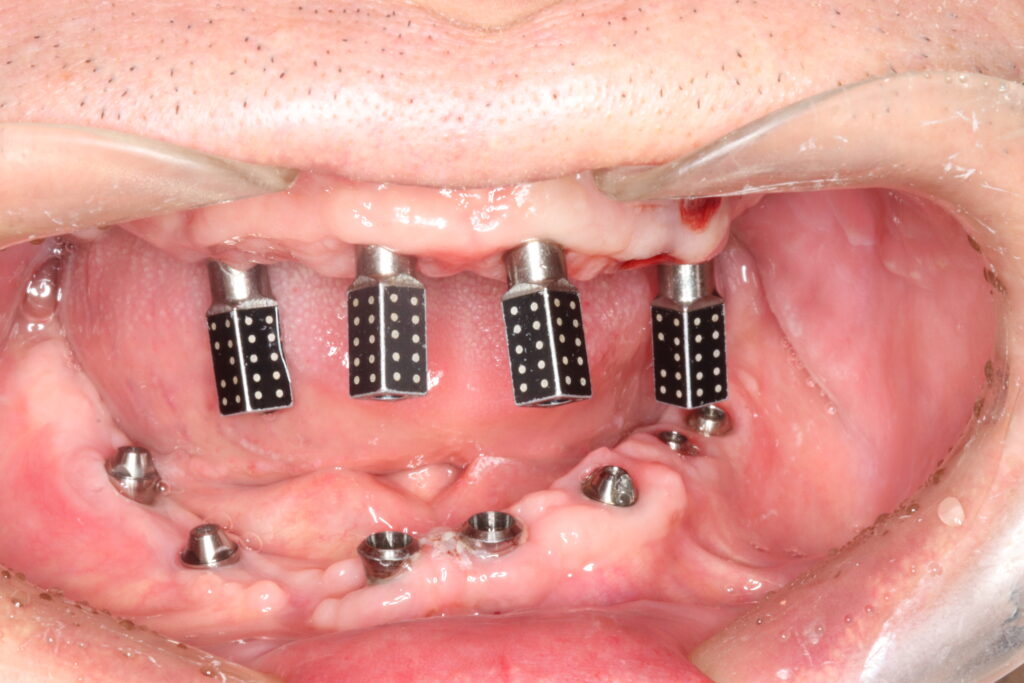

Fig.3: Extraoral photogrammetry, Icam4D [Imetric, Switzerland (3rd generation)]; (a) Icam4D radiopaque titanium SBs.

(b) EPG camera system combines structured light and photogrammetric scans to capture three-dimensional data

(c) The exact position of EPG scan bodies is automatically identified by the software